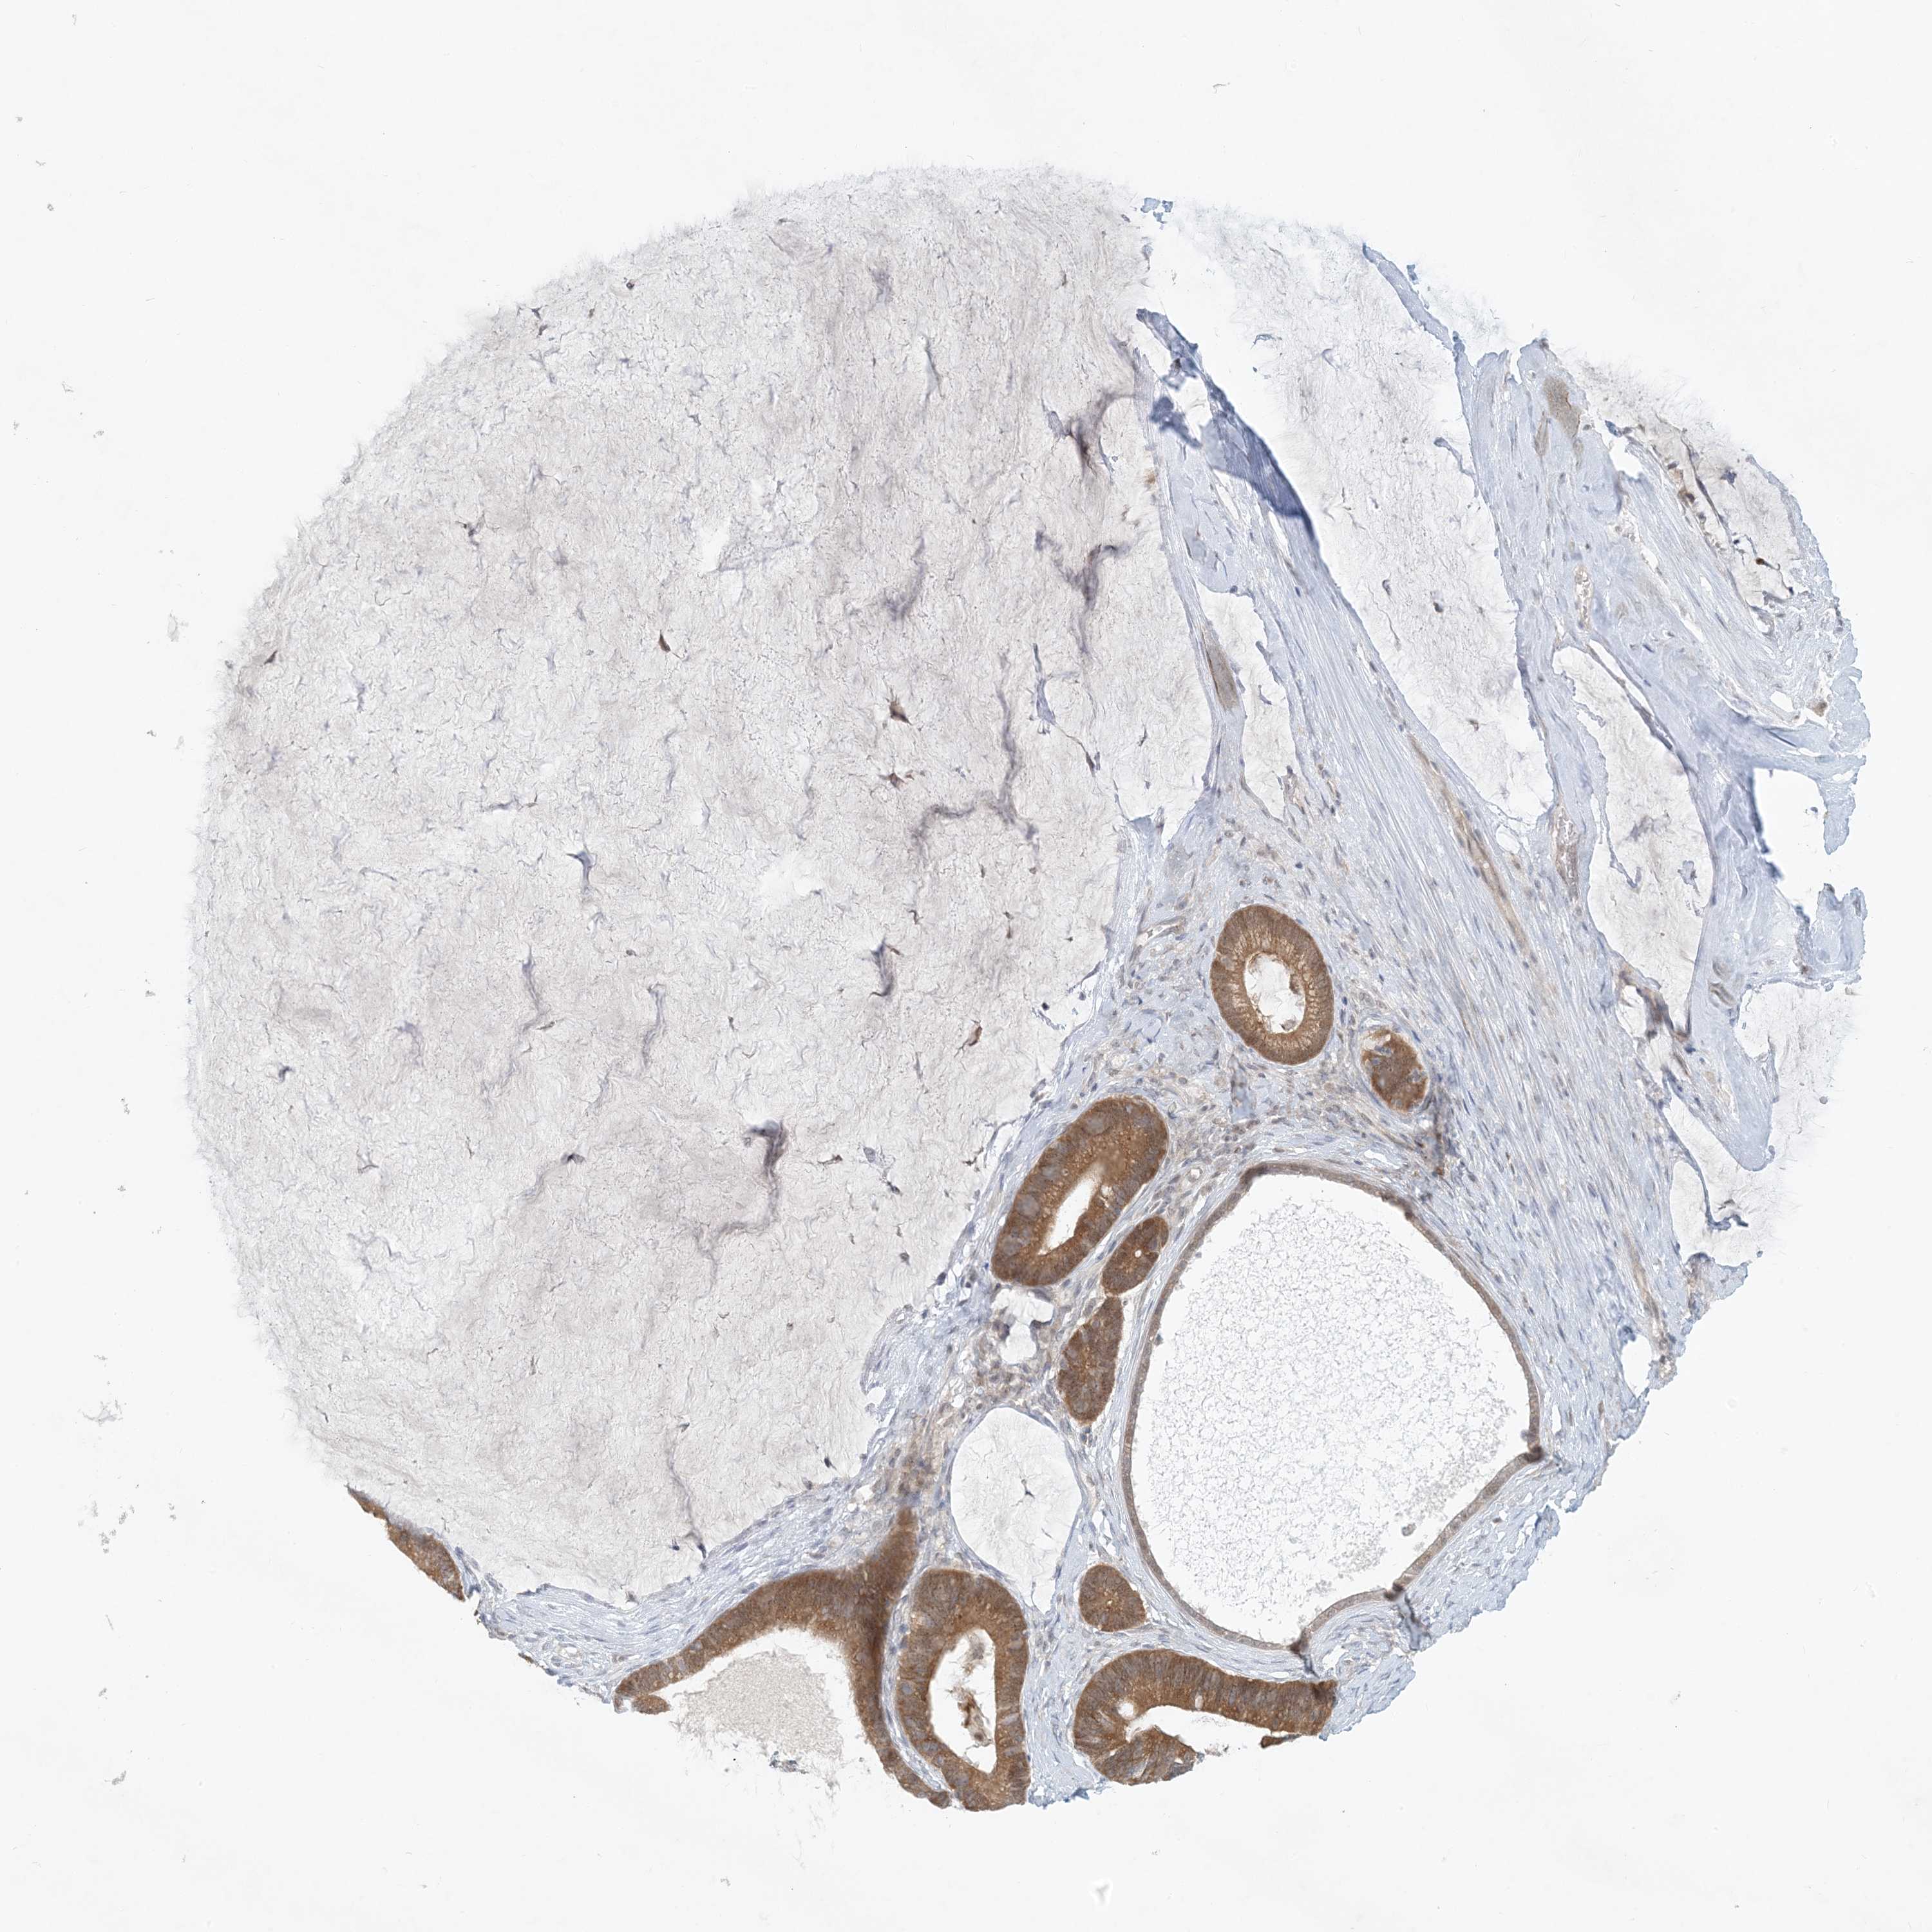

OVARIAN CANCER - Protein expressioni

A mouse-over function shows sample information and annotation data. Click on an image to view it in a full screen mode. Samples can be filtered based on level of antibody staining by selecting one or several of the following categories: high, medium, low and not detected. The assay and annotation is described here.

Note that samples used for immunohistochemistry by the Human Protein Atlas do not correspond to samples in the TCGA dataset.

Antibody stainingi

Antibody staining in the annotated cell types in the current human tissue is reported as not detected, low, medium, or high, based on conventional immunohistochemistry profiling in selected tissues. This score is based on the combination of the staining intensity and fraction of stained cells.

Each image is clickable and will lead to virtual microscopy that enables deeper exploration of all samples and also displays staining intensity scores, fraction scores and subcellular localization as well as patient and tissue information for each sample.

Antibody HPA034785

Antibody HPA034786

Cystadenocarcinoma, serous, NOS

Carcinoma, endometroid

Cystadenocarcinoma, mucinous, NOS

Carcinoma, NOS